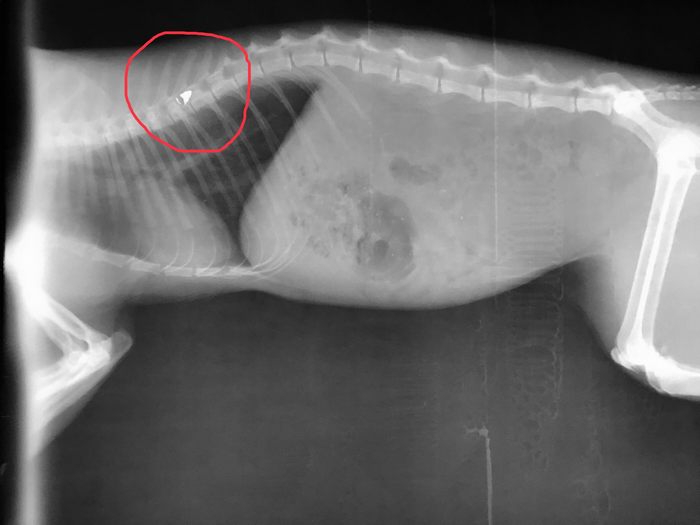

Σύμφωνα με τα όσα κατατέθηκαν ενώπιον των αστυνομικών και δικαστικών αρχών, ο εκπαιδευτικός που είναι και Λυκειάρχης σε σχολείο του δήμου Λαμιέων, πυροβόλησε το άτυχο ζώο με αεροβόλο, με τη βολίδα να σφηνώνεται στη σπονδυλική του στήλη και να μένει παράλυτο.

"Σε 16 μήνες φυλάκιση καταδικάστηκε σήμερα 12 Ιουλίου 2019 εκπαιδευτικός, διευθυντής σε Λύκειο της Δευτεροβάθμιας Εκπαίδευσης του Δήμου Λαμιέων, ο οποίος εν ψυχρώ πυροβόλησε και άφησε παράλυτο από την μέση και κάτω έναν αδέσποτο γάτο. Το άτυχο ζώο πυροβολήθηκε από τον δράστη με αεροβόλο όπλο την ώρα που ζευγάρωνε.